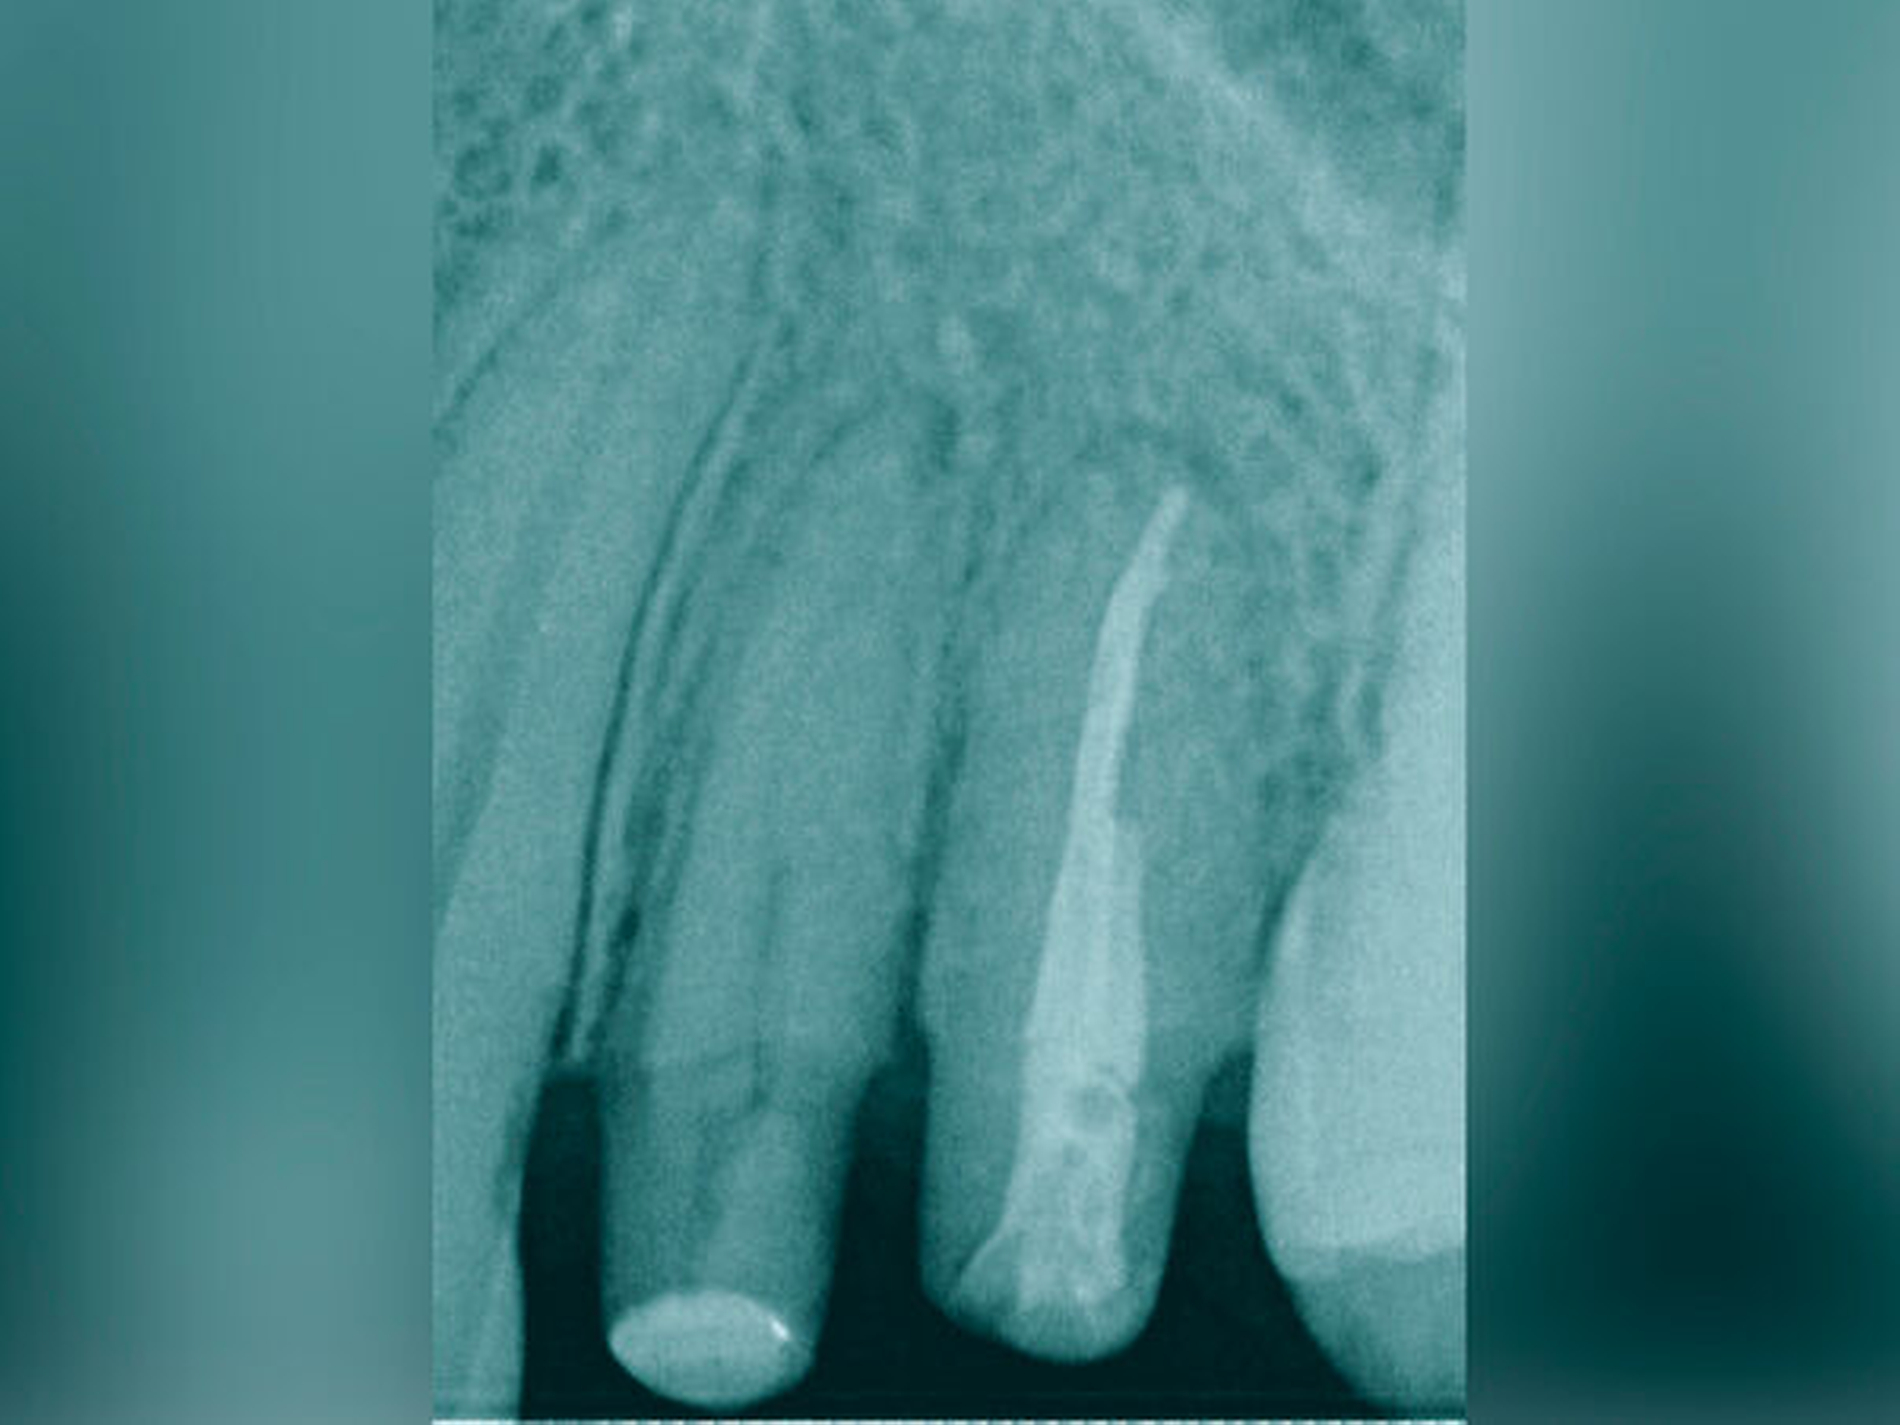

Eine weitere Möglichkeit, tief zerstörte Zähne möglichst schonend chirurgisch zu extrudieren, basiert auf axialen Zugsystemen (Abbildungen 2 bis 4). Diese erscheinen vorteilhaft bei sehr schwierigen Fällen, zum Beispiel bei Zähnen mit fehlendem Ansatzpunkt für die Zange sowie bei langen oder sehr ovalen Wurzeln. Axiale Zugsysteme ermöglichen die Übertragung von Zugkräften auf die Zahnwurzel, ohne die Alveole unnötig zu dehnen. Dazu wird eine spezielle Schraube in den Wurzelkanal eingebracht und das Gewinde der Schraube für eine ausreichende Friktion fingerfest eingedreht. An diese Schraube wird ein gerätespezifisches Zugsystem angelegt. Durch rein axial wirkende Zugkräfte werden traumatische Effekte auf Knochen und Wurzeloberfläche während der Zahnmobilisation minimiert. Gegebenenfalls können feine Luxatoren vorsichtig unterstützend eingesetzt werden. Im Tiermodell wurde an extrahierten und wieder replantierten Zähnen mit ovalem Querschnitt gezeigt, dass der Verlust von Zementoblasten auf der Wurzeloberfläche geringer ist, wenn ein axiales Zugsystem anstatt einer Extraktionszange verwendet wird.

Die wesentliche technische Komplikation stellt das unverhältnismäßige Erweitern des Wurzelkanals für die Retention des Zughilfsmittels – zum Beispiel der Benex-Schraube – dar. Der Behandler sollte hier unter besonderer Vorsicht den bereits instrumentierten und präparierten (vorgegebenen) Wurzelkanal als Bohr- und Zugpfad für die Extrusion nutzen. Auf die Schonung der gesunden Zahnhartsubstanz muss geachtet werden. Die Bohrachse für die Ausrichtung der Zugschraube muss mit dem koronal gelegenen Hauptpfad des Wurzelkanals übereinstimmen. Zudem ist für das Erzielen einer ausreichenden Retention der Schraube ein gewisses Maß an Feingefühl und Taktilität vom Behandler erforderlich. Eine neue Schraube erfüllt die Vorbedingung eines schneidfreudigen Gewindes und damit eines guten Halts im Zahn am besten.